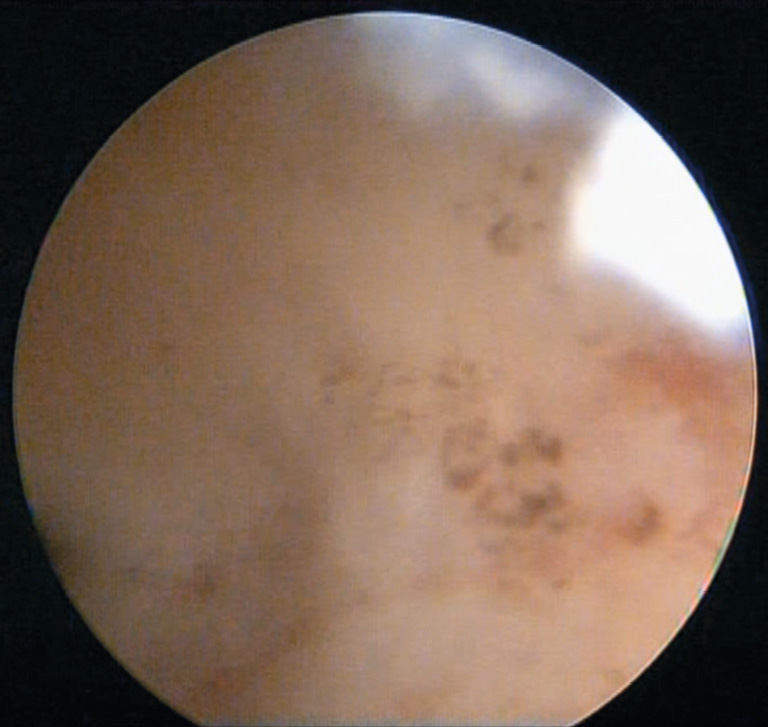

- Visual assessment of the uterine cavity and detection of intrauterine pathology. It should be kept in mind that adenomyosis can reveal different lesion patterns, including visible mouths (“passages” of adenomyosis) (Figure 1), sclerotic changes and synechiae, and diffuse myometrial changes (a “cobblestone sidewalk” appearance).

Fig. 1. Uterine cavity with adenomyosis foci